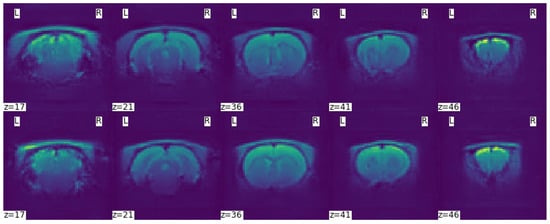

| Tests | Test1 | Test2 | Test5 | Test10 | Test11 | Test12 |

|---|---|---|---|---|---|---|

| Data sets | Dr174 | Dr174 Ds87 | Dr174 Ds348 | Dr174 Da826 | Dr174 Da348 | Dr174 Da348 |

| Global | 0.8969 | 0.9138 | 0.9141 | 0.8183 | 0.8742 | 0.8696 |

| GM | 0.9381 | 0.9419 | 0.9412 | 0.8856 | 0.9214 | 0.9190 |

| WM | 0.8969 | 0.9077 | 0.9098 | 0.7824 | 0.8585 | 0.8501 |

| CSF | 0.7468 | 0.8232 | 0.8180 | 0.6042 | 0.7100 | 0.7018 |